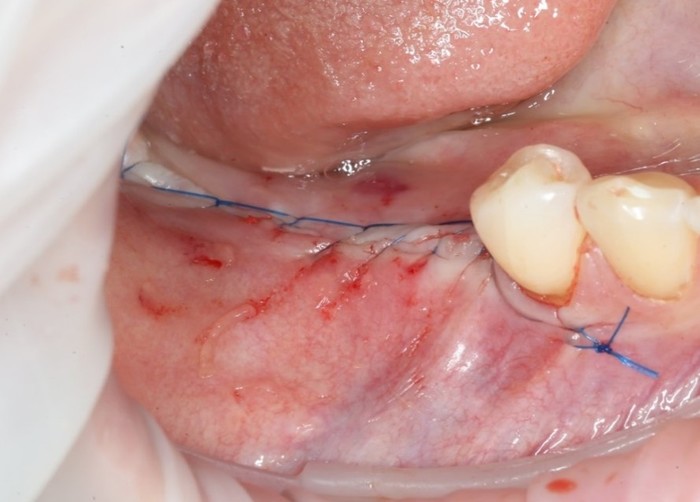

После нехитрых манипуляций мы прощаемся с Русланом на 4 месяца.

Этого времени достаточно на приживление имплантатов.

Снова была проведена профессиональная гигиена:

После чего пациент был направлен к ортопеду на слепки:

Спустя две недели произведена фиксация временных коронок.